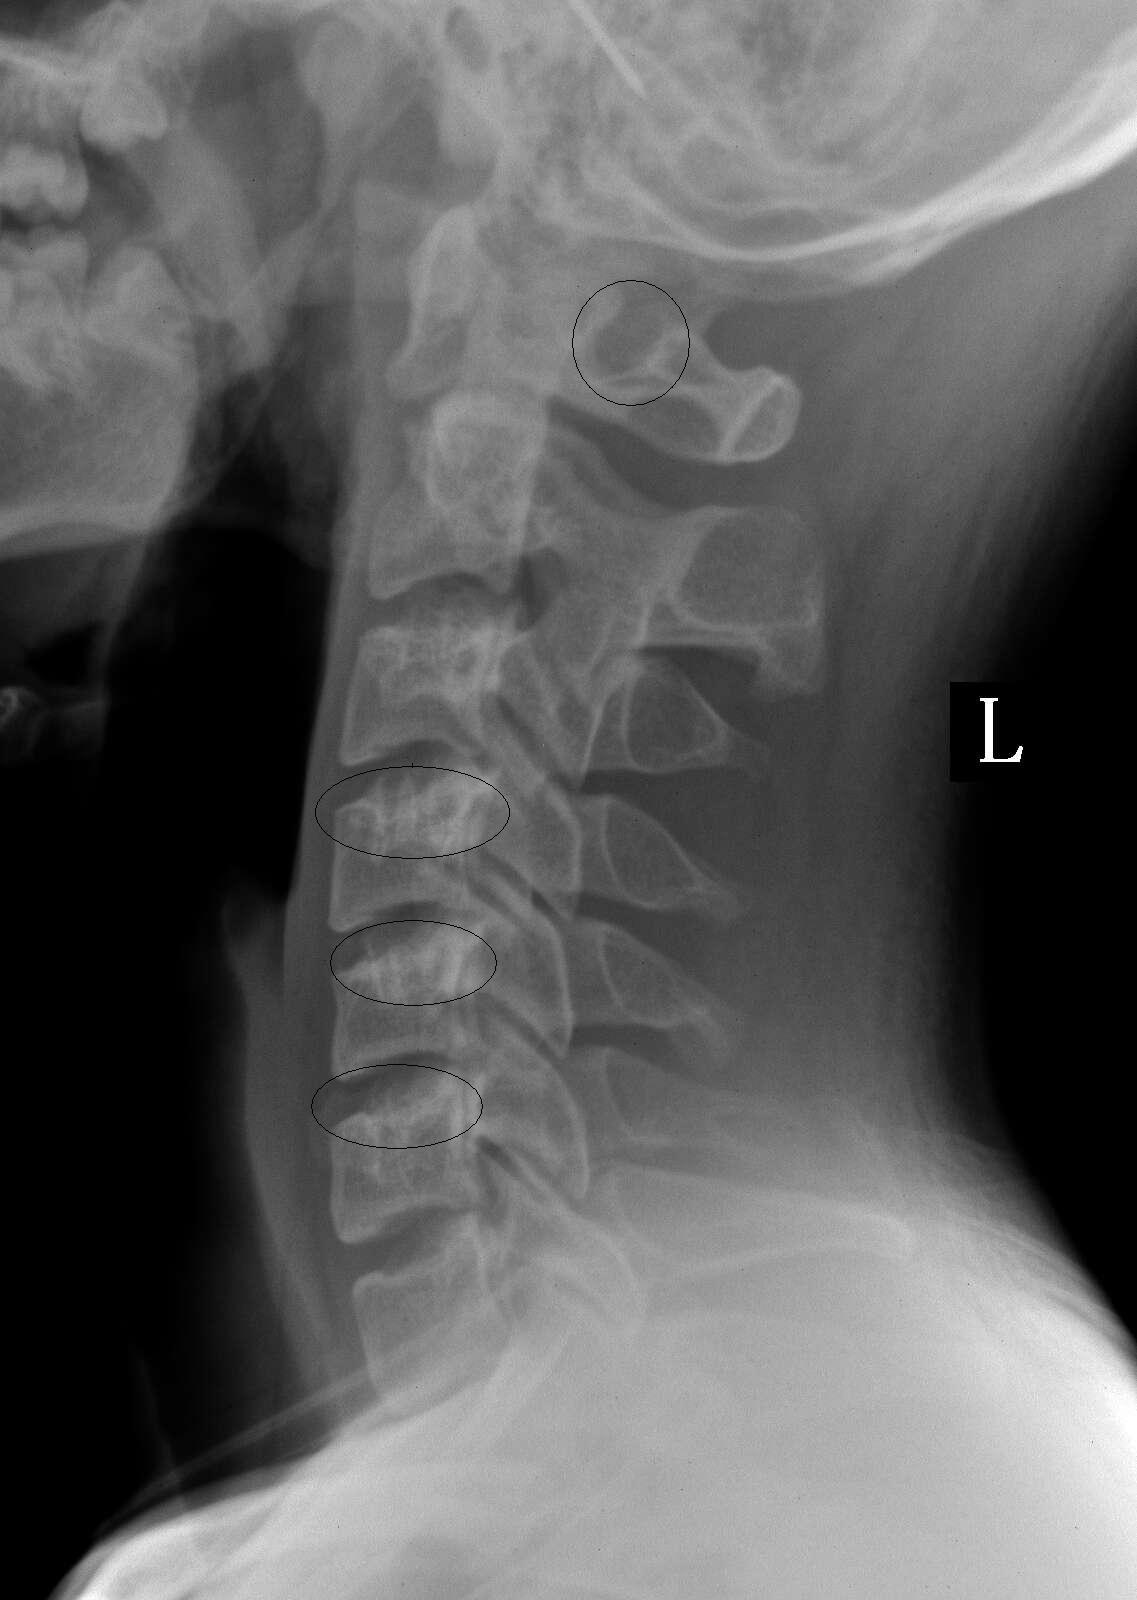

画的那四个圆圈里面是否有事,还是拍片时角度问题

可能与投照角度有关.不放心行ct平扫.

横突